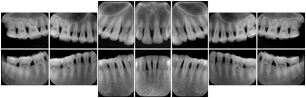

3. A dental provider wishes to capture a series of DICOM IO images for the patient’s dentition. The tooth morphology, teeth are divided into molars, premolars, canines and incisors, and a number of images for each jaw. The anatomic information was captured utilizing the triplet of schema. This standard code sequence is based on ISO 3950-2010, Dentistry - Designation system for teeth and areas of the oral cavity.

Every IO image should have anatomic information either through the primary or modifier sequence.

In most standard cases, images are oriented in structured layouts. These structured displays are useful to be shared between providers for reference purposes.

Table OO.1.1-1 shows structured display standard templates, where Viewset ID is based on the Japanese Society for Oral and Maxillofacial Radiology (JSOMR) classification provided by JIRA (Japan Medical Imaging and Radiological Systems Industries Association, www.jira-net.or.jp). Expected or typical teeth to be imaged location, region and designation codes are based on ISO 3950-2010, Dentistry - Designation system for teeth and areas of the oral cavity. For all the hanging protocols listed in OO.1.1-1, the value to use for Hanging Protocol Creator (0072,0008) is "JSOMR" and the value to use for Hanging Protocol Name (0072,0002) does not include "JSOMR" (e.g., "DL-S001A", not "JSOMR DL-S001A").

Table OO.1.1-1. Hanging Protocol Names for Dental Image Layout based on JSOMR classification